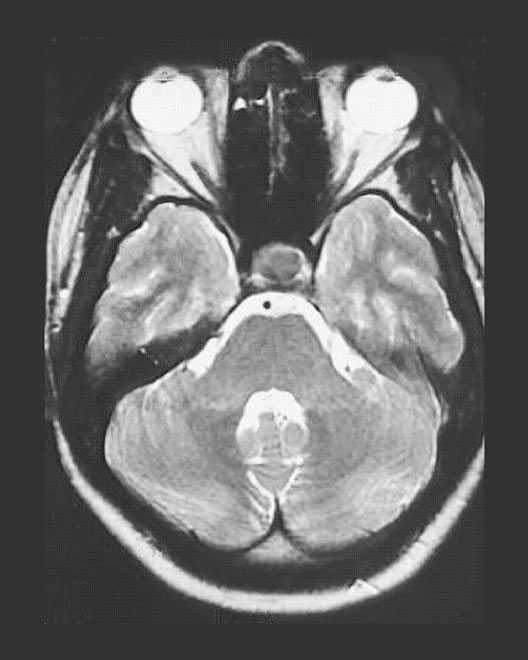

Head MRI

Roll mouse over image to display labels.

1. Sphenoid Air Sinus

2. Hypophysis

3. Basilar Artery

4. Fourth Ventricle

5. Eyeball

6. Optic nerve

7. Temporal lobe gray matter

8. Temporal lobe white matter

9. Pons

10. Cerebellum